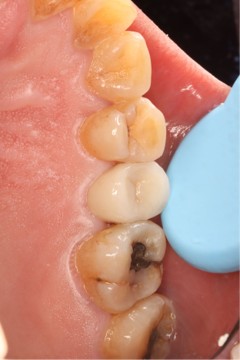

June 20, 2025: The patient's chief complaint is that endodontic treatment was performed on the right maxillary posterior tooth abroad, and a deep carious lesion has been recently detected, requiring restoration. The following are the intraoral photographs taken upon the patient's first visit: a large carious lesion is visible on the occlusal surface of tooth 15 (FDI numbering), with only the buccal wall remaining. Percussion test and cold-hot stimulation test showed no response, and yellow obturation material is visible at the root canal orifices.

September 19, 2025: Delivery of zirconia post and core + all-ceramic crown for tooth 15; the margins are well-adapted with no occlusal high points, and the patient reported comfortable occlusion.